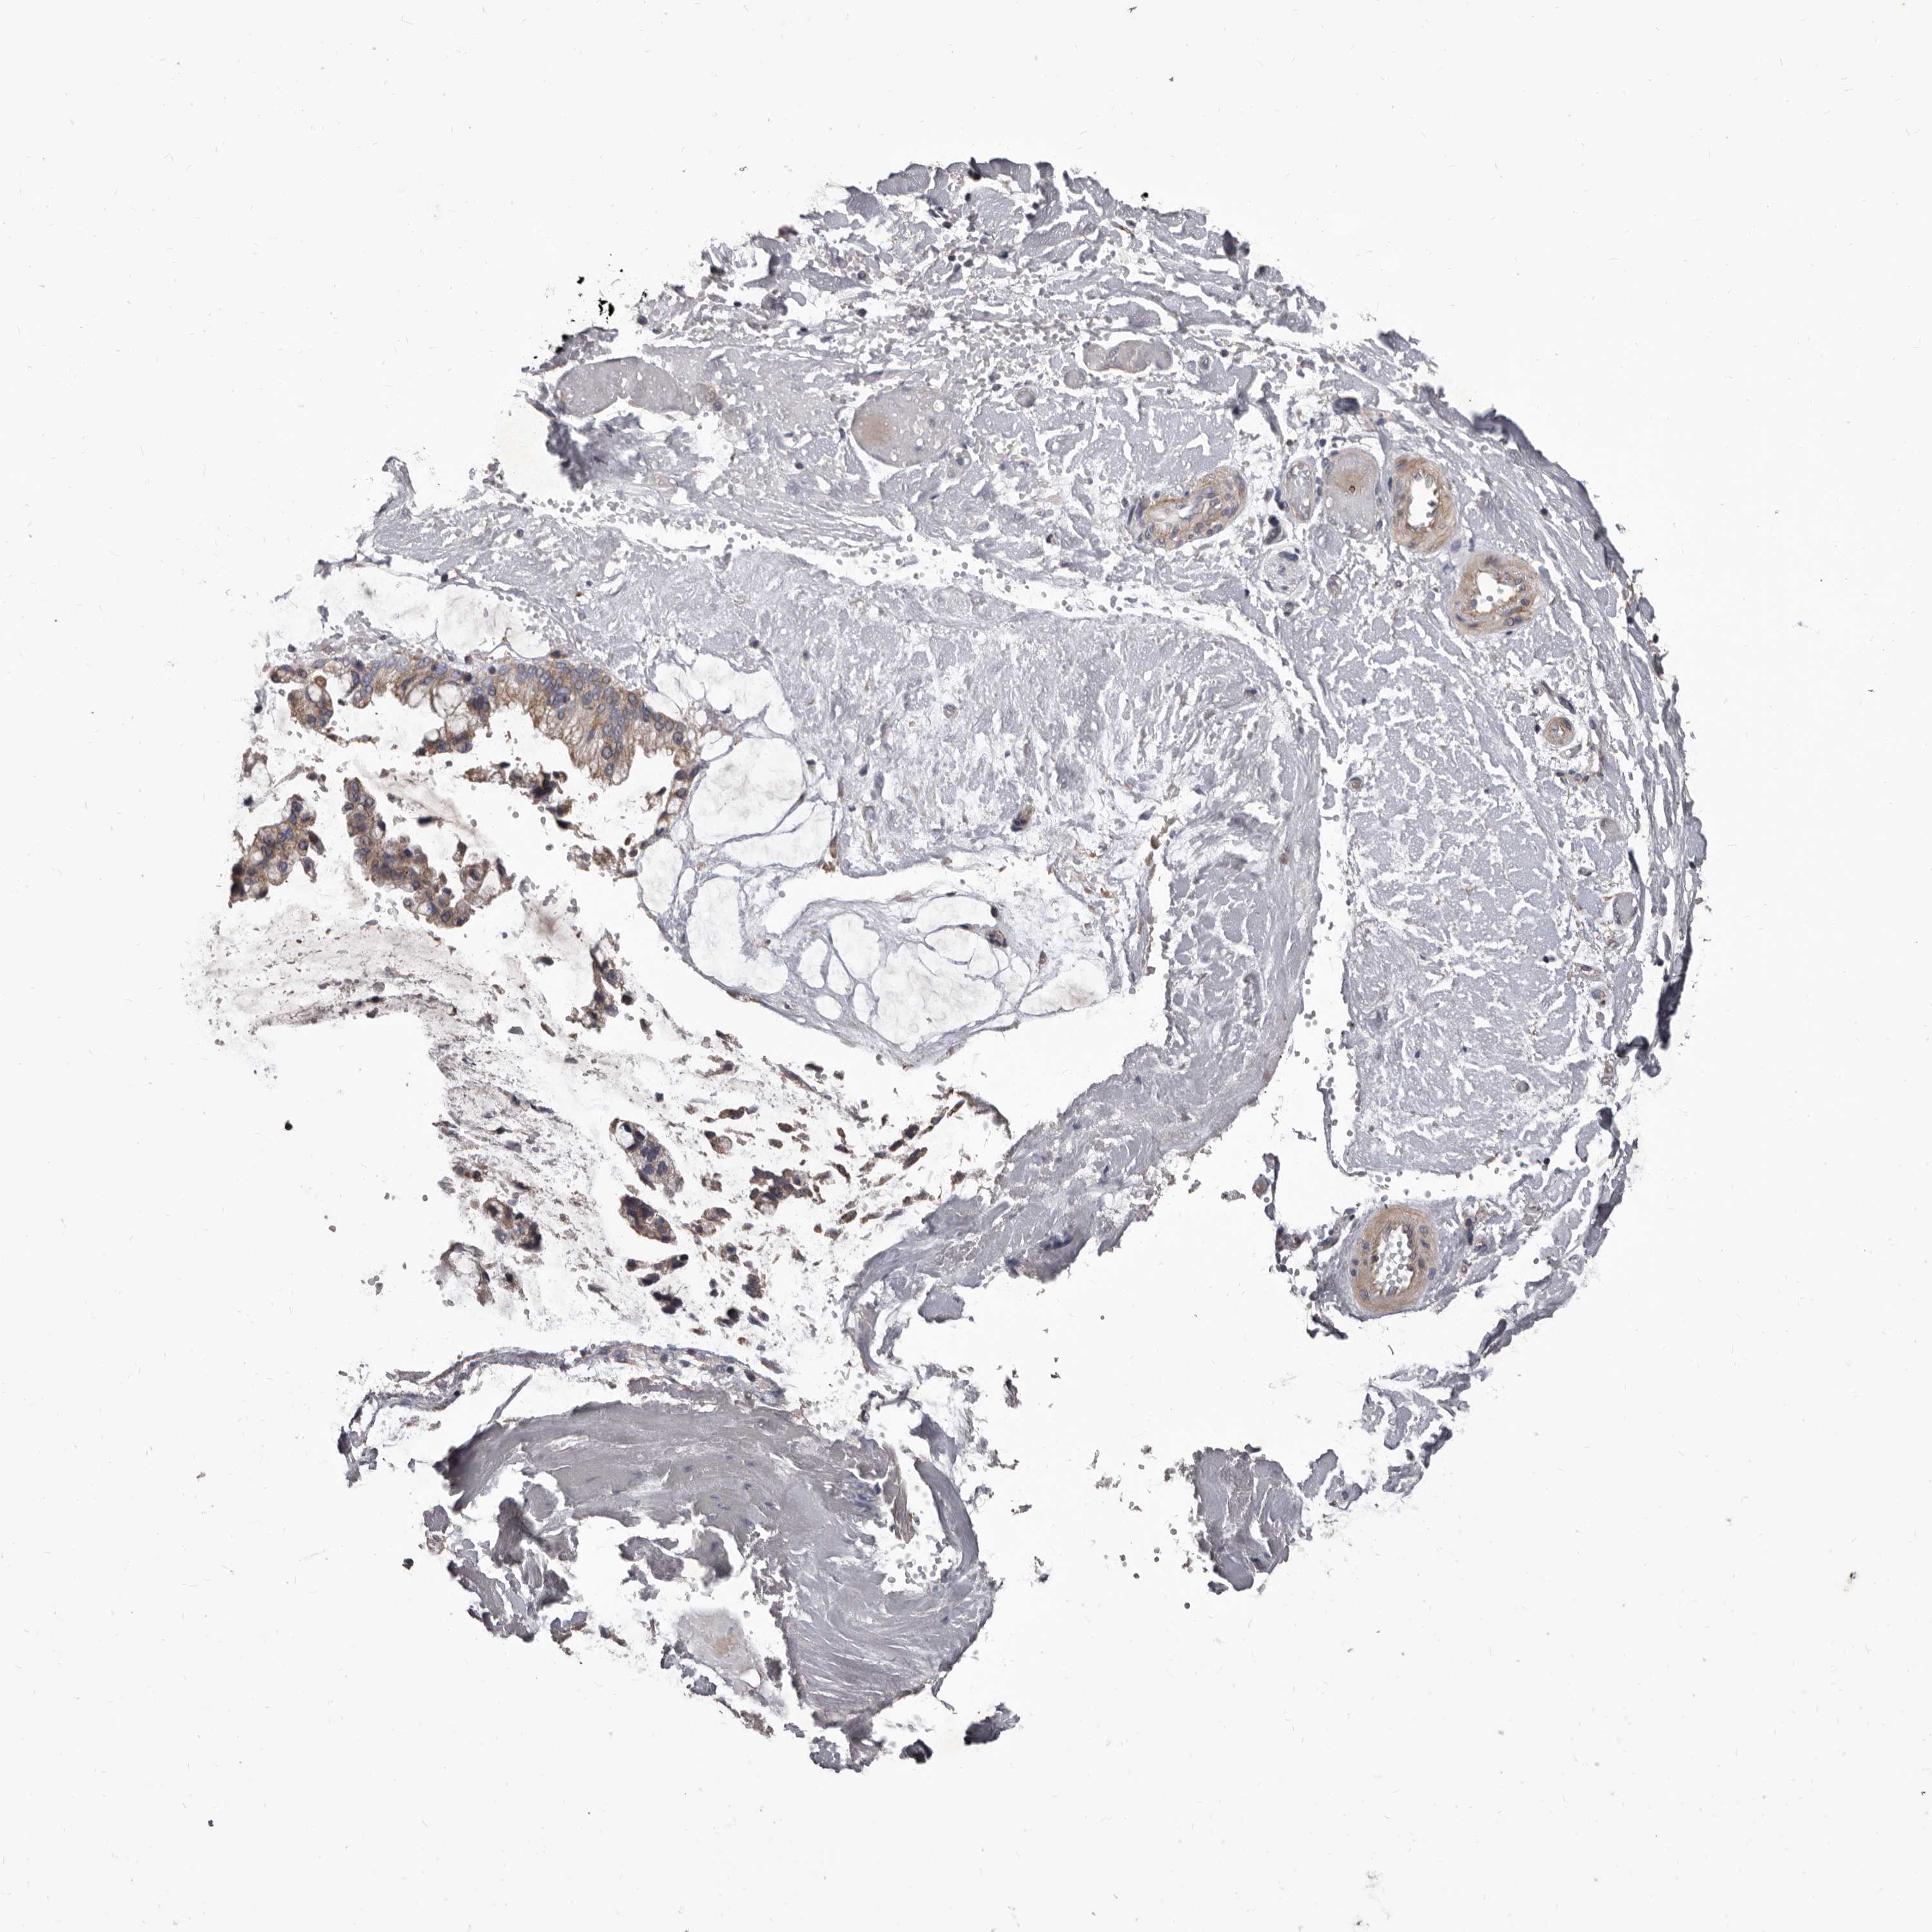

OVARIAN CANCER - Protein expressioni

A mouse-over function shows sample information and annotation data. Click on an image to view it in a full screen mode. Samples can be filtered based on level of antibody staining by selecting one or several of the following categories: high, medium, low and not detected. The assay and annotation is described here.

Note that samples used for immunohistochemistry by the Human Protein Atlas do not correspond to samples in the TCGA dataset.

Antibody stainingi

Antibody staining in the annotated cell types in the current human tissue is reported as not detected, low, medium, or high, based on conventional immunohistochemistry profiling in selected tissues. This score is based on the combination of the staining intensity and fraction of stained cells.

Each image is clickable and will lead to virtual microscopy that enables deeper exploration of all samples and also displays staining intensity scores, fraction scores and subcellular localization as well as patient and tissue information for each sample.

Antibody HPA029715

Antibody HPA029716

Cystadenocarcinoma, serous, NOS

Carcinoma, endometroid

Cystadenocarcinoma, mucinous, NOS

Carcinoma, NOS